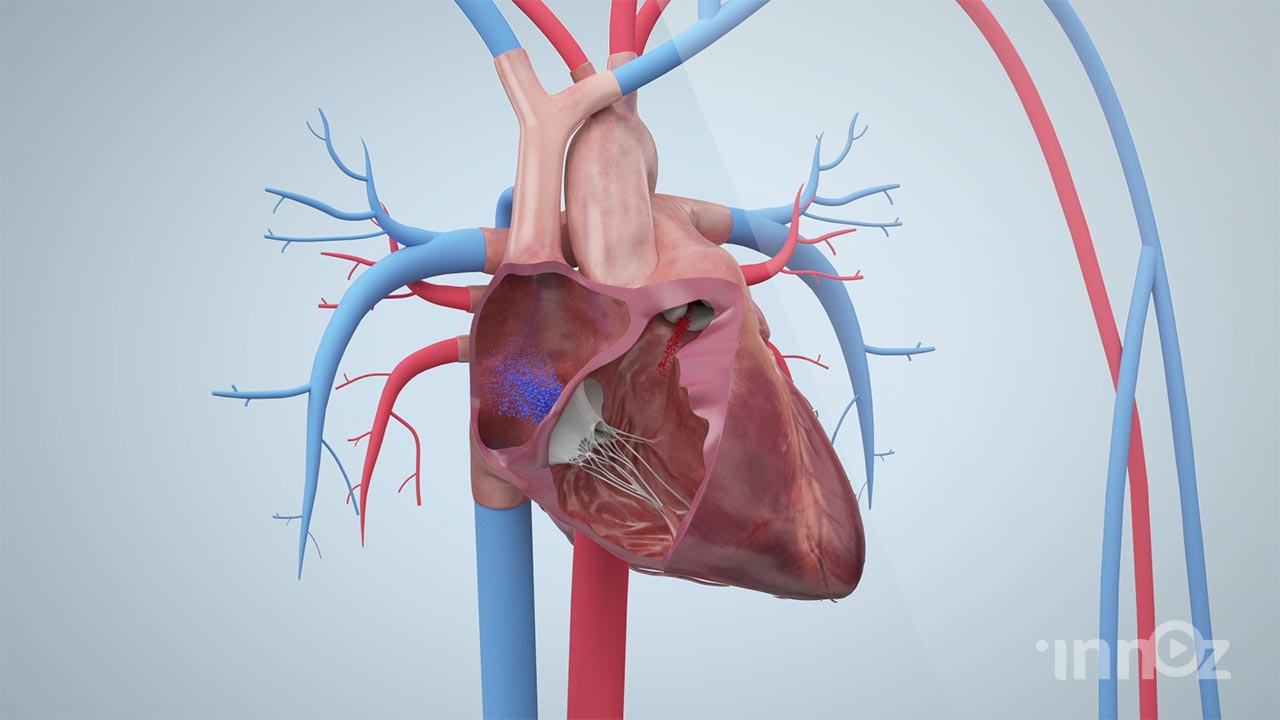

의료, 건설, 산업, VR AR, AI 등 고퀄리티 3D영상제작

이노즈는 AI영상제작, 3D영상 제작 전문기업으로, 다양한 산업 분야에 걸쳐 혁신적이고 몰입감 있는 3D 콘텐츠를 제공합니다. 제품 홍보, 건설 시뮬레이션, 애니메이션 등 맞춤형 영상으로 고객사의 가치를 시각적으로 효과적으로 전달합니다. 고품질의 3D 시각화와 창의적인 연출을 바탕으로, 고객의 목표를 실현하는 독창적이고 강력한 시각적 경험을 제공합니다. 이노즈의 포트폴리오는 고객의 아이디어를 현실로 구현한 다양한 성공적인 프로젝트로 가득합니다.

2021 아리바이오 뇌 세포 영상제작

2020 삼진제약 암세포제거 영상제작